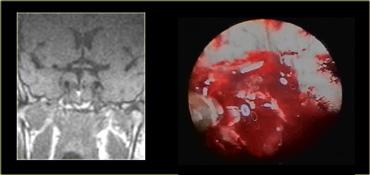

Các hình ảnh này mô tả phẫu thuật cắt bỏ u tuyến yên đại tuyến qua đường xuyên bướm (transsphenoidal resection).

Sau khi phần sàn xương của hố yên được lấy bỏ, màng cứng (dura) được rạch bằng đường rạch hình chữ thập.

Do áp lực phía trên màng cứng lớn hơn áp lực phía dưới, khối u đại tuyến sẽ tự thoát ra vào xoang bướm (sphenoid sinus).

Chụp MRI trong mổ được thực hiện trong một bối cảnh thử nghiệm để xác định xem phẫu thuật viên thần kinh có lấy bỏ thành công toàn bộ khối u hay không.

Do việc sử dụng đường phẫu thuật này có trường nhìn hạn chế, điều quan trọng là phải biết trước mình đang phẫu thuật trên tổn thương gì.

Như chúng ta sẽ thấy, có những tổn thương mà bạn không nên phẫu thuật theo đường tiếp cận này!